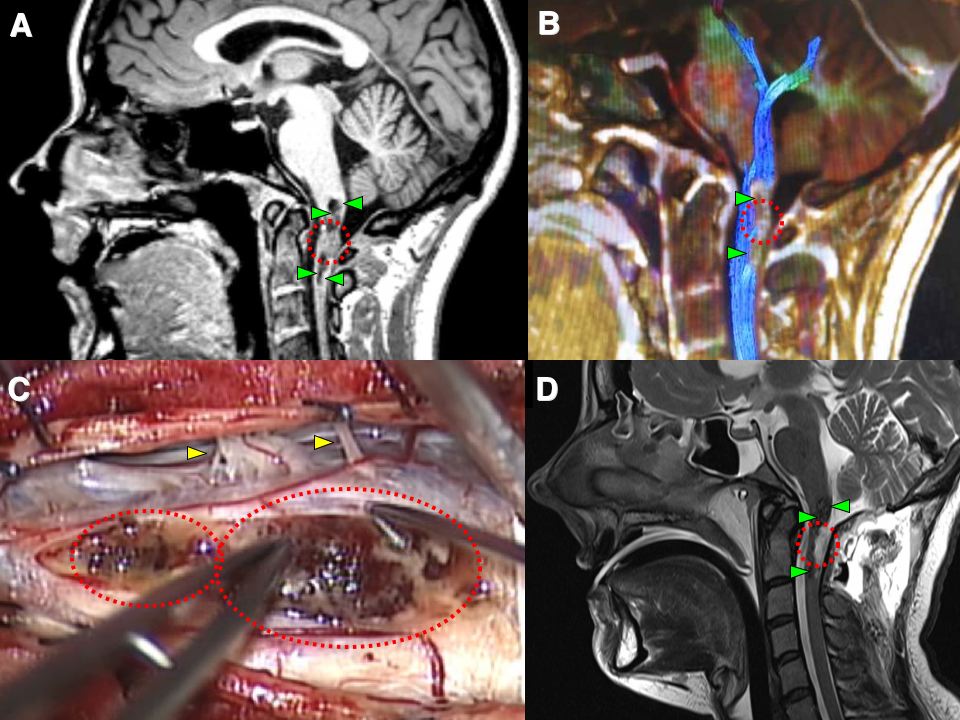

Much less commonly a cavernoma may be found in the spinal cord (but this may be more likely to occur in patients with a family history of cavernous malformations). The image collage below shows a cavernoma in the uppermost part of the cervical spinal cord before and after successful microsurgery by Dr Khurana (post-operative images lower right – D – in the panel below):